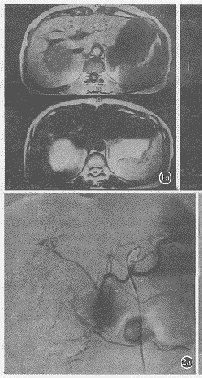

MR平扫:6例肾上腺嗜铬细胞瘤,右侧5例,双侧1例,大小为5~13cm,平均8.2cm,病灶呈类圆形或圆形。T1WI上低于肝脏信号,T2WI上则明显高于肝脏信号,信号不均匀,边缘尚清晰。5例主要波及肝右叶后段和肾上极,其中2例见囊变坏死信号(图1);另1例主要波及胰头并包绕下腔静脉。

图1 瘤体上下部轴位MR T1WI及T2WI (a、b);冠状位T2WI,显示瘤体呈圆形,边缘清晰,呈长T1长T2信号,中见囊变坏死信号,瘤体波及肝右叶及右肾上极,误诊为巨块型肝癌(c)。

MRI显示瘤体呈圆形或类圆形,边缘较清晰,与包膜成分有关。T1WI上低于肝脏的信号强度,T2WI上呈明显高信号,高于脂肪的信号强度,可能与病灶含丰富的血管及含水量较多有关。因肿瘤常伴出血、坏死及囊变,信号常不均匀[3,5]。Reinig等发现嗜铬细胞瘤在T2WI中,其与肝脏的信号强度之比大于3.4,明显高于肾上腺其他肿瘤。本组6例均表现此类信号特点,其中2例见囊变及坏死信号。